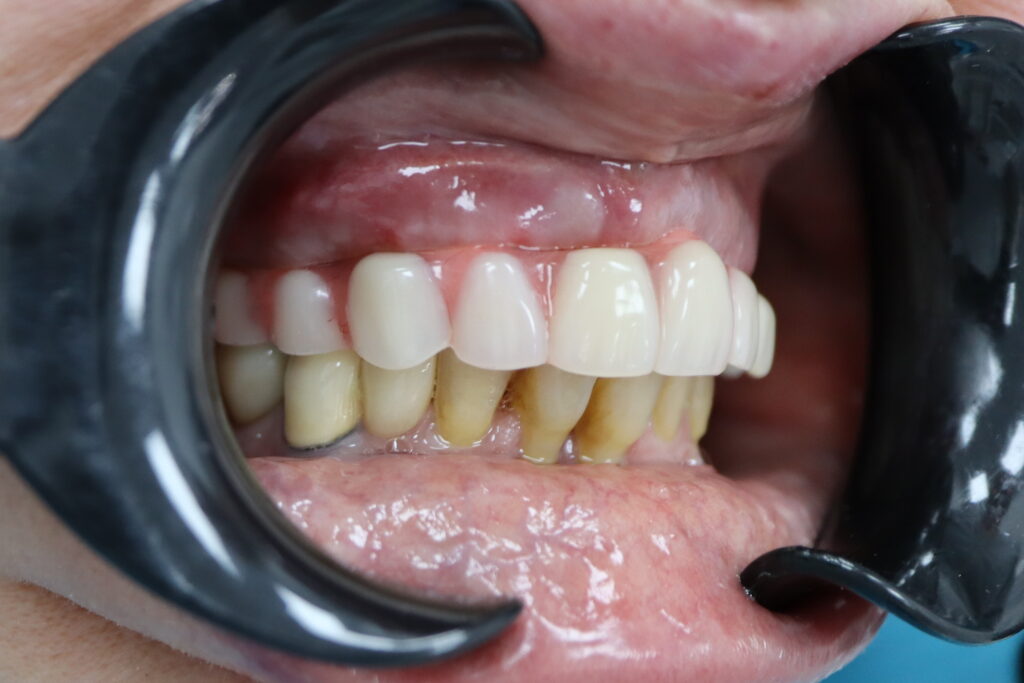

Результаты

результат имплантации